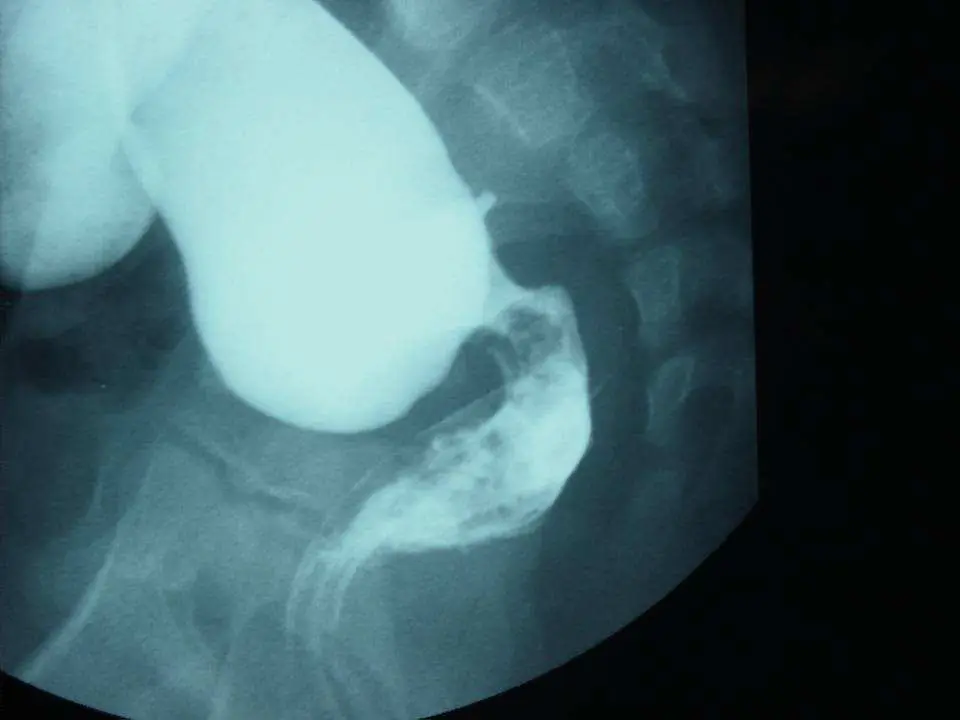

本題影像與上題相同,為同一位新生兒的下消化道鋇劑攝影(barium enema)側位影像。

影像發現(同上題):

- 典型的近端腸道擴張合併遠端直腸/乙狀結腸移行區(transitional zone)

- 近端大口徑充鋇腸管(正常有神經節細胞段,繼發性擴張)

- 遠端狹窄段(aganglionic segment,功能性痙攣)

本題影像作為「承上題」的參照,確認診斷為巨結腸症後,進一步評估手術選項。